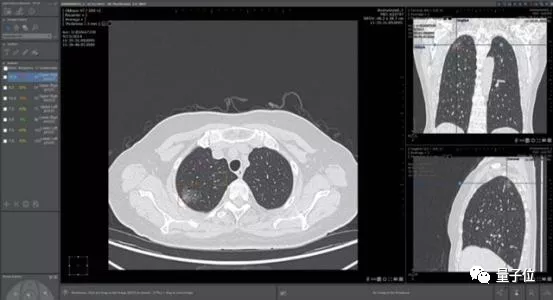

医疗影像辅助诊断是当时医疗 AI 公司扎堆投入的领域。这家公司最大的卖点肺结节诊断,则是红海中的红海。

一家医院接入 4、5 家 AI 肺结节诊断产品成了司空见惯,曾有影像医师笑称:

中国人的肺结节都不够用了。